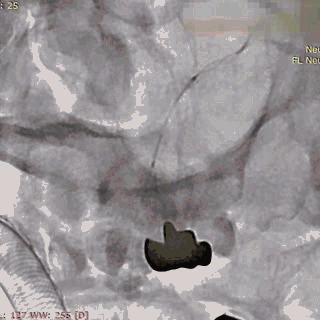

支架远端打开。

支架远端打开情况。

支架中段打开,过50%释放标记点。

造影显示支架整体打开良好。

支架完全释放。

微导管沿推送杆通过支架,撤出推送杆,保留通路。

造影显示支架打开良好,准备桥接第二枚支架。